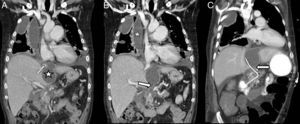

Paciente varón de 47 años con antecedente de pancreatitis crónica con seudoquiste pancreático que ingresa por cuadro constitucional, vómitos, fiebre y dolor torácico pleurítico. En la TC observamos derrame pleural bilateral loculado con un trayecto fistuloso transdiafragmático entre el seudoquiste y el conducto pancreático y una colección paramediastínica derecha (fig. 1).

A y B) Reconstrucciones coronales de la TC en paciente de 47 años con antecedente de pancreatitis crónica complicada con fístula pancreato-torácica. La TC muestra un derrame pleural loculado (estrella en B) con comunicación (flecha en A) con el seudoquiste (estrella en A) que a su vez conecta con el Wirsung (flecha en B). C) La TC de control realizada a los 12 días, tras CPRE con colocación de prótesis (flecha en C) que drena el seudoquiste y la colección pleural a través del Wirsung a duodeno.

Tras los hallazgos se colocan tubos de drenaje pleural bilaterales obteniéndose líquido con citología inflamatoria aguda y amilasa elevada. Se coloca una prótesis pancreática por CPRE (fig. 1).